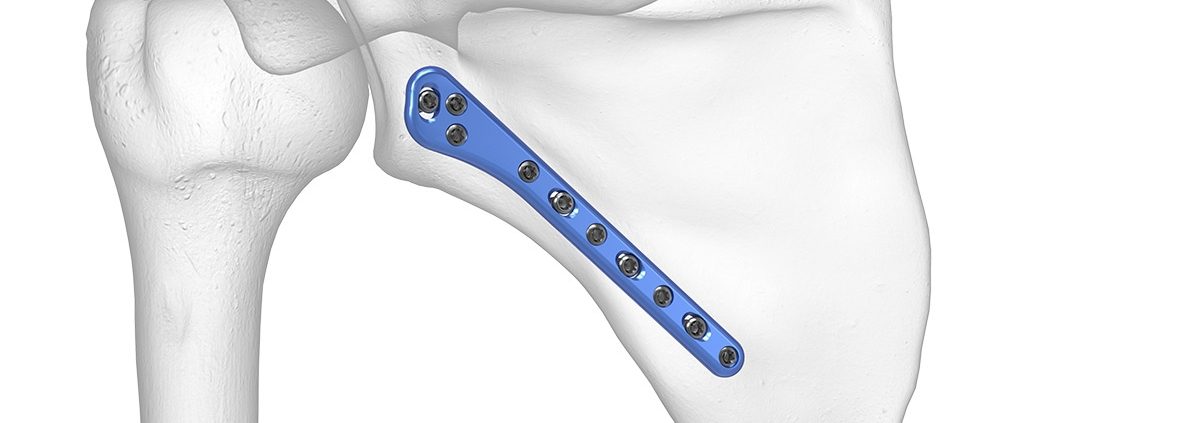

Tratamentul chirurgical este indicat în fracturile deplasate, în cele care implică semnificativ cavitatea glenoidă sau în cazurile de instabilitate articulară. Intervenția constă, de regulă, în reducerea anatomică și fixarea internă cu plăci și șuruburi, având ca scop restabilirea congruenței articulare și a funcției umărului.